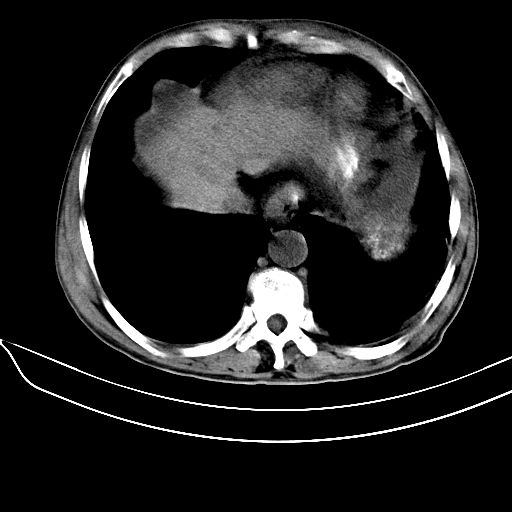

肝硬化可以明确,至于脾脏轻度增大,内部见大量钙化,考虑:脾脏感染性病变(脾脏脓肿,寄生虫或爱滋病等. )后的改变可能性大.

肝硬化、腹水,脾广泛不均匀高密度影原因?应密切结合病史,病人有没有感染史及造影史?如果都没有可考虑脾海绵状血管瘤钙化。

肝硬化、腹水,脾广泛不均匀高密度影原因?应密切结合病史,病人有没有感染史及造影史?如果都没有可考虑长期肝硬化导致的淤血性脾内钙化。